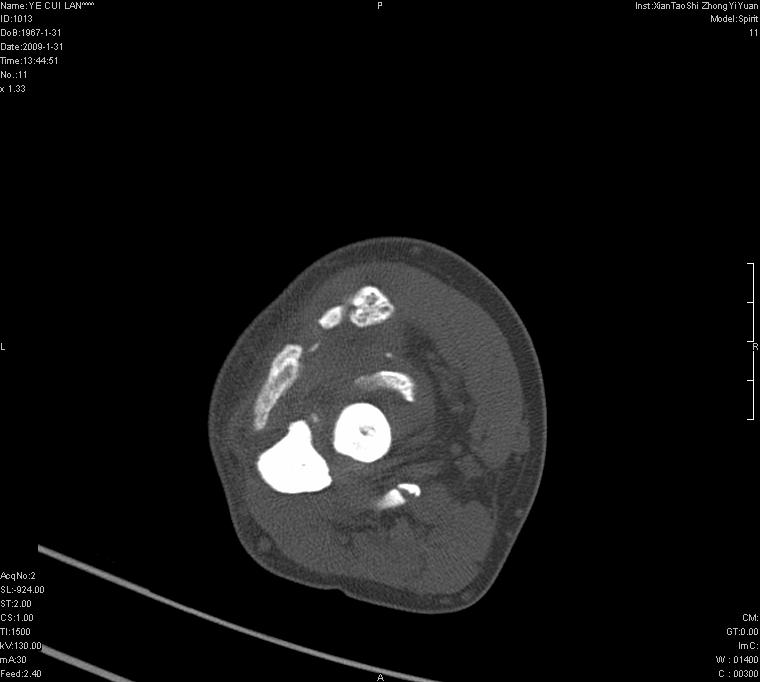

以下是引用王明发在2009-2-9 11:53:00的发言:[br]支持夏科氏关节,必要时行脊髓mri检查 [br]夏科氏关节是指由于某些神经系统疾病引起的关节病变,也被称为神经性关节炎。常见病因有脊髓痨、脊髓空洞症等。原发的神经病变可以造成关节深部感觉障碍,对于关节的震荡、磨损、挤压、劳倦不能察觉因而也不能自主地保护和避免,而神经营养障碍又可使修复能力低下,使病人在无感觉状态下造成了关节软骨的磨损和破坏,关节囊和韧带松弛无力,易形成关节脱位和连枷关节。关节面的破坏和骨赘的脱落变成关节内游离体。关节外形饱满肿胀,内有出血和渗出。这种病早期并无疼痛,不易被病人重视,仅表现为关节肿胀、无力、活动过度、动摇不稳。关节肿胀、无痛、活动范围超常是本病的重要特征。x光片可见有关节骨端广泛破坏、硬化或呈奇异形态,骨赘形成,关节间隙不规则或增宽,周围软组织钙化、关节内游离体、骨碎片等。结合x光片及临床症状,病人又有神经系统原发病症,即可确诊

以下是引用hhcckk在2009-2-9 14:31:00的发言:[br]夏科关节的六大表现[br]1.关节软组织肿胀。[br]2.关节的脱位与半脱位。[br]3.关节内的游离体。[br]4.关节面硬化,新骨形成。[br]5.骨质萎缩与破坏。[br]6.关节结构的紊乱。[br]加上患者无明显疼痛,诊断的把握性比较大